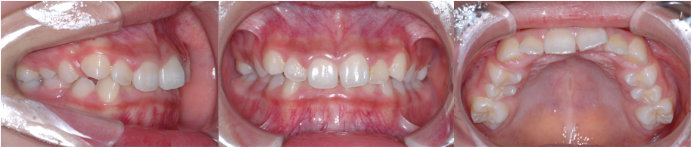

| Case1 |

| 出っ歯 |

| <治療前> |

| <治療後> |

| 主訴 |

前歯が出ている |

| 診断名 |

上顎前突 |

| 年齢 |

8歳 |

| 使用装置 |

マルチブラケット装置 |

| 抜歯部位 |

永久歯の抜歯は無し |

| 治療期間 |

2年4か月 |

| 治療費概算 |

検査・診断料:5万円+税 装置・技術料:25万円+税 おおよそ1か月ごとの処置・管理料:5,000円+税 保定装置料:5万円+税 |

| リスク・副作用 |

う蝕 歯根吸収 |